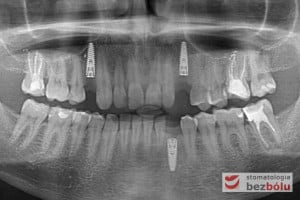

Procedurę chirurgiczną rozpoczęto od sprawdzenia przylegania szablonów do zębów pacjenta oraz znieczulenia miejscowego. W kolejnym kroku, przy pomocy specjalnie przeznaczonego do tego celu zestawu wierteł, wypreparowano krążki dziąsła punktowo odsłaniające kość a następnie poprzez tuleje prowadzące, z najwyższą precyzją, opracowano łoże implantu. Kulminacyjny moment zabiegu, czyli wprowadzenie wszczepów MIS C1 również odbyło się poprzez szablon, gwarantując precyzyjną lokalizację implantów. Zwieńczeniem całej procedury było przyszycie uprzednio wypreparowanych krążków śluzówkowo-okostnowych. Tuż po zabiegu, celem weryfikacji poprawnej pozycji implantów, wykonano zdjęcie ortopantomograficzne. Podczas wizyt kontrolnych, pacjent nie skarżył się na żadne dolegliwości bólowe, nie wystąpił obrzęk, a zreponowane we właściwych miejscach fragmenty dziąsła nie wykazywały oznak martwicy, co świadczyło o ich ponownym ukrwieniu i wgojeniu się. Wszystkie te przesłanki jasno wskazują na skuteczność zastosowania techniki komputerowej nawigacji w implantologii.